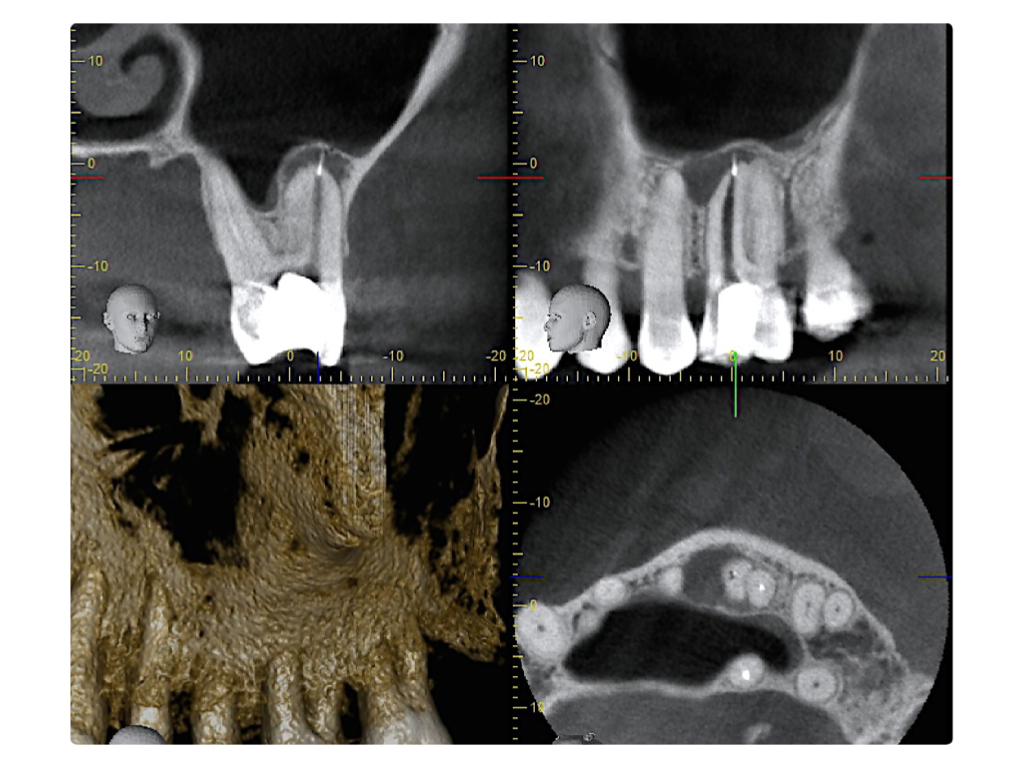

WS8.007

Instrumentenfraktur (3a)